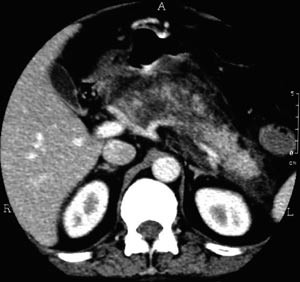

I tillegg til teksten er studiane vurdert systematisk i e-tabell 2 (5, 7) – (10, 12). Det vanlege inklusjonskriteriet i studiane er CT-påviste nekrosar i pancreas (fig 1 – 4) saman med klinisk akutt pankreatitt.